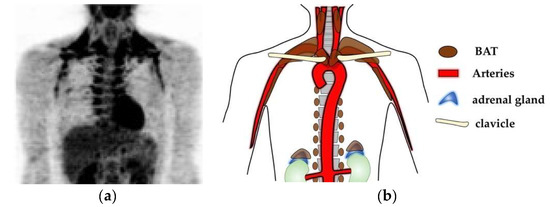

Brown adipose tissues (BATs), which contribute to non-shivering thermogenesis, has been attracting attention as a target for therapeutic development against obesity and metabolic disorders. BATs are required for the maintenance of body temperature in a cold environment in small mammals, which suffer from large heat loss due to high surface/volume ratios. BATs also contribute to rapid thermogenesis after hibernation. In mice, the presence of BATs has been anatomically determined in specific sites of the body including in interscapular, cervical, axillary, perirenal, and mediastinal regions [1,2] as well as in mammary gland [3]. Humans also have functional BATs [4,5,6,7], whose distribution has been visualized by 18F-fluorodeoxyglucose (18F-FDG)-PET/CT examinations as fat depots with high glucose uptake capacities. In adult humans, BATs are detected in deep neck regions, supraclavicular regions, axillary regions, paravertebral regions, periaortic regions, and suprarenal regions (Figure 1). The localization of BATs can be summarized as “alongside of large arteries” and “in peri-adrenal gland spaces”, both of which receive abundant adrenergic signals. Since adrenergic stimuli are required for the maintenance of BATs, this distribution pattern of BATs seems highly reasonable.

Figure 1. BATs are located alongside of large arteries and in peri-adrenal gland spaces. (a) A 18FDG-PET/CT examination result of a young adult with acute cold exposure at 19 °C for 2 h. Adopted from Figure 7B in Reference [14].; (b) Schematic presentation of body BAT localization in humans. BATs are located in deep neck regions, supraclavicular regions, axillary regions, paravertebral regions, and periaortic regions, which can be summarized as alongside of large arteries, as reported in the case of deep neck BAT [35], and in suprarenal regions, which have been determined as peri-adrenal gland spaces [36]. These regions receive abundant adrenergic signals, which contribute to the maintenance of BAT.